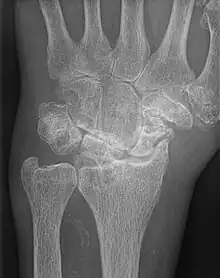

| AP wrist x-ray demonstrating Stage III scapholunate advanced collapse | |

Stage III SLAC wrist

Stage III SLAC wrist involves the entire radioscaphoid joint and the capitolunate joint.[3] The PA wrist x-ray will demonstrate sclerosis and joint space narrowing between the lunate and capitate. Over time, the capitate will migrate proximally into the space created by the scapholunate dissociation.[2] The radiographic findings in Stage III SLAC wrist are synonymous with the Terry-Thomas sign, indicating complete scapholunate dissociation.[2]